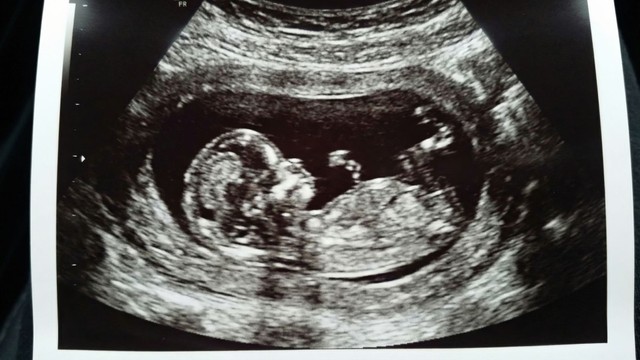

Sự phát triển của thai nhi